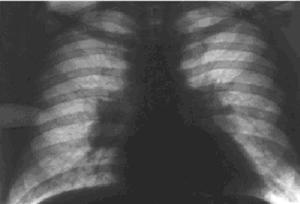

Рис. 1. Рентгенограмма грудной клетки больного саркоидозом внутригрудных лимфатических узлов. Корни легких расширены, значительное двустороннее увеличение внутригрудных лимфатических узлов, преимущественно бронхопульмональных. Умеренно выраженное усиление легочного рисунка в прикорневых отделах.